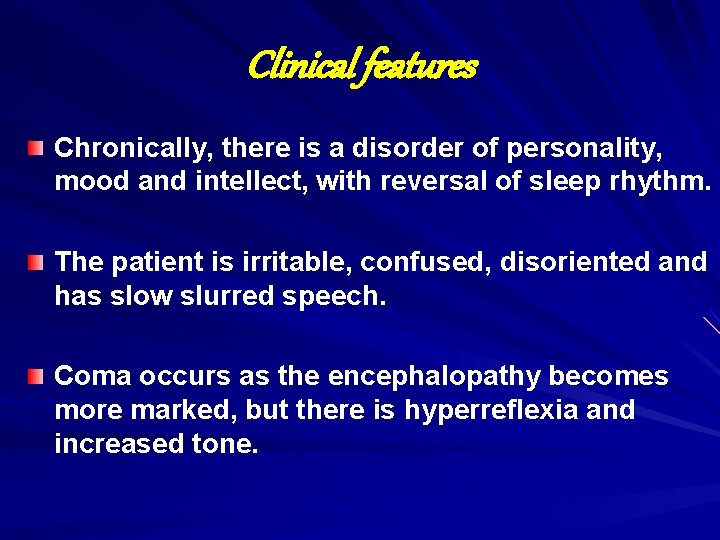

Clinical features Chronically, there is a disorder of personality, mood and intellect, with reversal of sleep rhythm. The patient is irritable, confused, disoriented and has slow slurred speech. Coma occurs as the encephalopathy becomes more marked, but there is hyperreflexia and increased tone.